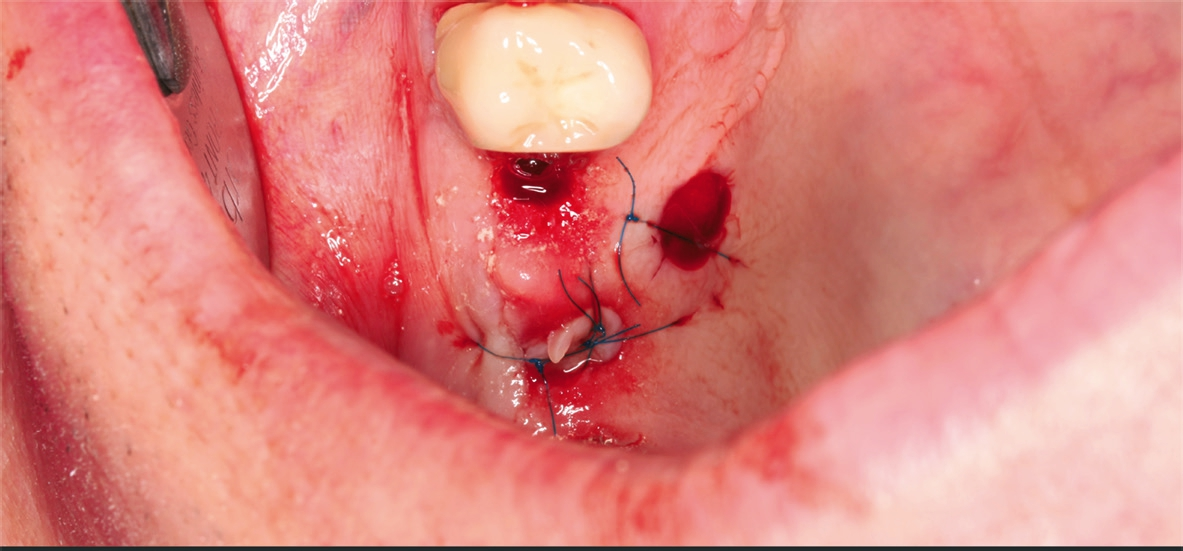

Patient 3: weiblich, 62 Jahre alt, Anamnese: unauffällig; spezielle Anamnese: Zustand nach chronischer schwerer Parodontitis; Diagnose: nicht erhaltungswürdiger Zahn 16, Freiendsituation. Knochenersatzmaterial: maxgraft® (botiss) (Abb. 13 bis 15).

Dr. van Orten